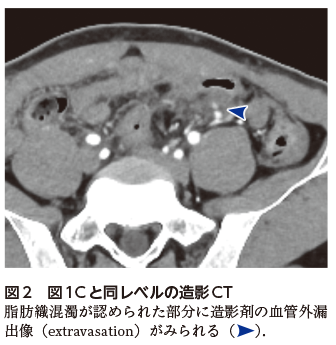

なお,本例は初回のCT検査の段階で造影CT(図2として本頁にのみ掲載)も実施されており,腸間膜での造影剤の血管外漏出像(extravasation)が認められていたためすみやかに治療へと移行できた.しかし,単純CTのみで評価していた場合には,重篤性を過小評価してしまう恐れがあった.